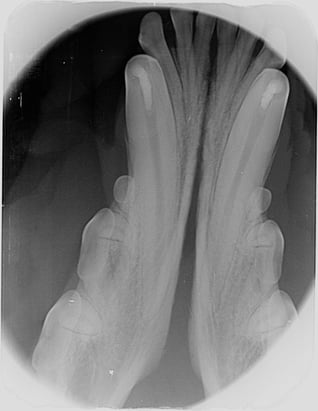

Radiography is important to confirm the position and degree of resorption of the deciduous teeth to be extracted. Like all deciduous dentition, the tooth roots are extremely long in comparison to the length of the crowns. This is especially dramatic in deciduous canine and incisor teeth: the roots of these teeth could be as much as four to six times the length of the crown. For better visualisation, an open technique is advisable. The complete extraction of the deciduous canines is important in interceptive orthodontic procedures, as retained root remnants could still affect the position of the permanent succedaneous canine teeth. Post-operative radiography to confirm complete extraction in these cases is therefore important.